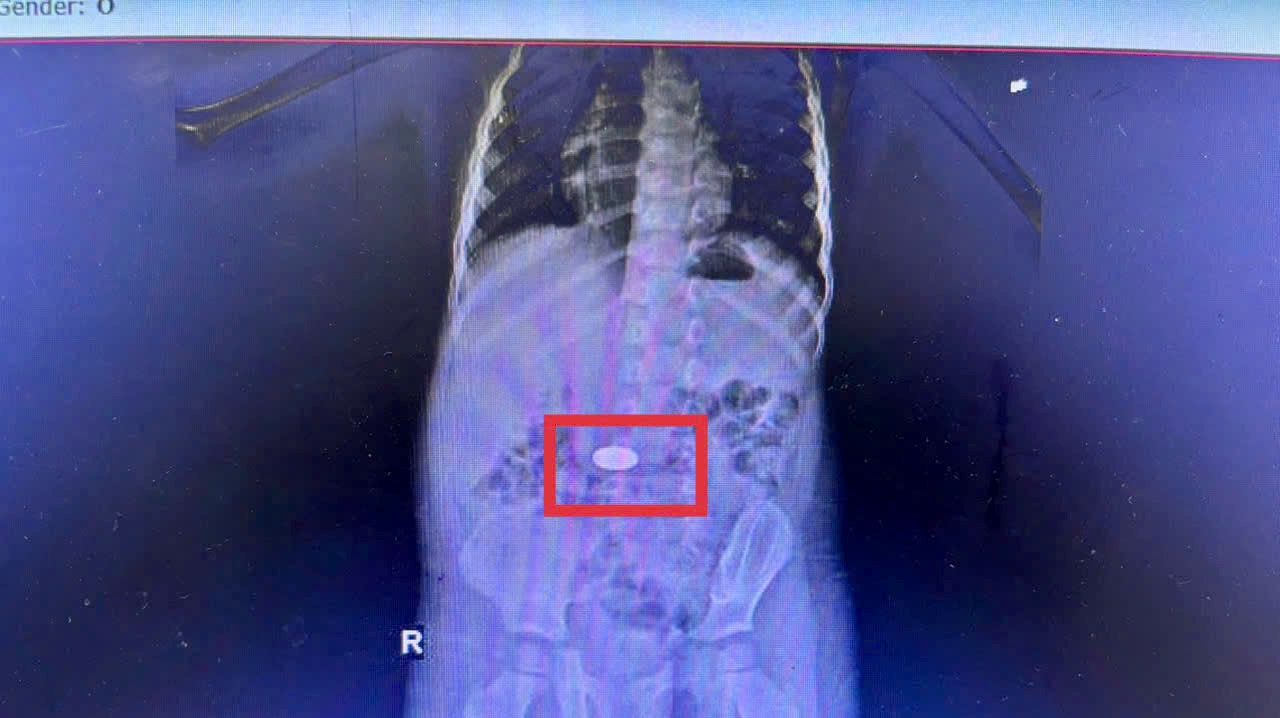

CT scan shows that the foreign object has entered the stomach. Doctors quickly performed an endoscopy and removed the coins in the early morning of November 26. After treatment, the child recovered well and was discharged from the hospital the next day.